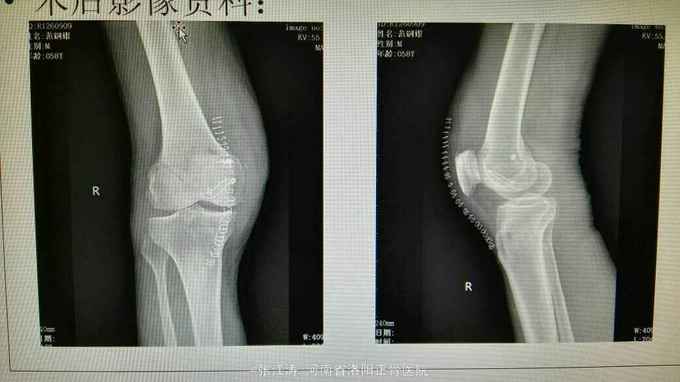

车祸致伤膝关节脱位3天住院,受伤后未做相应处理,仅行MRI检查。

膝关节前后抽屉试验及外翻应力实验阳性,末梢血液循环及感觉运动良好

膝关节脱位,前后交叉韧带损伤及内侧副韧带损伤